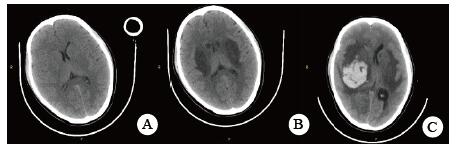

当晚20时到达本院,入院时患者昏迷,血压低、心肌损伤、轻度心衰, 低氧血症, 肝损伤。相关实验室检查:血气PaO2 44 mmHg,生化指标谷丙转氨酶(ALT)528.8 U/L,谷草转氨酶(AST)780.9 U/L,胆红素正常,尿素氮(BUN)3.6 mmol/L,肌酐(Cr)125.7 μmol/L,血糖7.88 mmol/L,心肌肌酐蛋白(cTnT)55.94 ng/mL,N末端B型利钠肽原(NT-pro BNP)495.7 pg/mL,神经元特异性烯醇化酶(NSE)47.46 ng/mL。胸部CT未见明显异常(图 1),头颅CT未见明显异常(图 2A)。给予异甘草酸镁保肝,乙酰半胱氨酸抗氧化,兰索拉唑保护胃黏膜,并予血液灌流治疗一次。

| A:入抢救室当日(中毒首日);B:住院第5天(中毒第6天);C:住院第8天(中毒第9天) 图 2 患者头颅CT影像 |

次日晚间收住入院。住院第2天监测血压99/72 mmHg。实验室检查:cTnT 245.4 ng/L,NT-pro BNP 18.57 pg/mL,BUN 2.68 mmol/L,Cr 40.5 μmol/L,血钾3.82 mmol/L。血气:PO2 116 mmHg,pH 7.498, Lac 1.58 mmol/L。并CRRT治疗:治疗前APTT为32.2 s,阿加曲班抗凝,治疗剂量40 mL/(kg·h)。第3天继续CRRT治疗,阿加曲班抗凝,监测APTT为62.9 s(为正常值2倍)。第4天停CRRT, 记录自发尿量1 920 mL /24 h。第5天神志逐步转清,有指令动作,自主呼吸良好,停机械通气。脱机拔管后查颅脑CT双侧基底节区及脑干低密度影, 考虑中毒性脑病改变(图 2B),胸部CT未见明显异常。监测APTT为26.7 s。第7天患者再次昏迷,并有呼吸急促,脉氧下降。再次行气管插管呼吸机支持。监测肝功能进一步好转(ALT 187.7 U/L,AST 92.2 U/L)。第8天17时发现患者瞳孔不等大,左侧3.5 mm,右侧4.5 mm, 对光反射消失,即查颅脑CT示右侧基底节区出血(图 2C)。家属要求保守治疗。第9天患者处于深昏迷状态,家属放弃继续治疗出院。出院一周后随访患者死亡。

哒螨灵口服中毒后机体细胞内呼吸功能抑制,导致细胞缺氧,无糖酵解,乳酸快速堆积,机体迅速出现代谢性酸中毒,重要脏器灌注不足,早期即可表现肝功能异常甚至肝衰竭;心肌酶谱增高,心肌收缩力减低,胰腺功能受损,血淀粉酶增高,血糖应激性增高[3]。由于人体脑组织供应的血流非常丰富,因此对缺氧表现也非常敏感。但哒螨灵中毒并发脑病报道较少,并发脑出血者罕见。该例患者中毒后出现恶心呕吐,提示该药对胃肠道有刺激性;后出现多系统损伤。早期即出现意识障碍,并渐加重至昏迷,有脑神经元损伤,但早期头颅CT未见明显异常;患者有严重低血压,需要大剂量血管活性药物维持血压;患者严重低氧血症,需要呼吸机支持,但肺部影像学未见明显异常;患者有乳酸酸中毒、肝肾功能损伤和心肌受损,但上述损伤大多在支持治疗2~4 d后完全正常或出现明显好转。但第5天头颅CT提示患者出现中毒性脑病表现,患者神志在短暂好转后又再次恶化,第8天原右侧基底节区水肿部位出现脑出血。